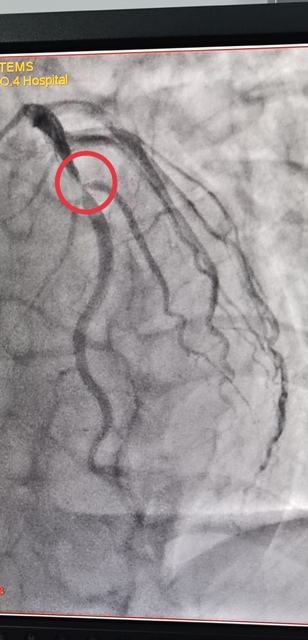

45岁的郭先生,一周前无明显诱因出现胸前区疼痛,伴有胸闷、心悸,疼痛发作时间持续10分钟后自行缓解,伴有大汗淋漓,来21点策略指南站 心血管内科就诊诊断为“冠心病不稳定性心绞痛”,于2021年1月3日早上10点进入导管室,实施了冠脉造影术 经皮冠状动脉内支架植入术,心内科主任王选琦主任医师介绍说,这是省四院第一例648元支架手术,手术进展顺利,患者术中、术后无不适症状,术后病症明显缓解,目前在心内科治疗观察。

陕西省第四人民21点基本策略 于2021年1月1日零时执行国家组织冠脉支架集中带量采购中选结果,据悉,中选的冠脉支架产品的平均价格由原来的7500元降至648元。为确保患者在2021年1月1日当天能够使用中选产品,陕西省第四人民21点基本策略 迅速贯彻省市医保局要求,已经将中选支架采购安排到位,从2021年1月1日0时开始实施新的价格标准。郭先生是蓝田人,成为新年第一个享受国家医改福利的人。